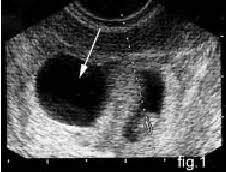

Confirming Multiple Gestations Using Ultrasound Empowered Women S Health

Confirming Multiple Gestations Using Ultrasound Empowered Women S Health from images.takeshape.io

Ultrasound uses sound waves to create an image of your babies in the womb. I just had my ultrasound. What are the symptoms of twins in first trimester? Seven weeks in already, and everything's going so fast. It depends on your situation. I was just hoping the baby had a super strong heartbeat! 4d ultrasound pregnancy 7 weeks twins full screen. Wow you are expecting quads?? 600 x 450 jpeg 35 кб. 4d ultrasound 7 weeks gestation 4d embryo download me (it´s free) my gear clínica ginecologica dr. My 10 week ultrasound revealed a vanishing twin. 7 week ultrasound boy vs girl. My twin pregnancy faq camp counselor mom.